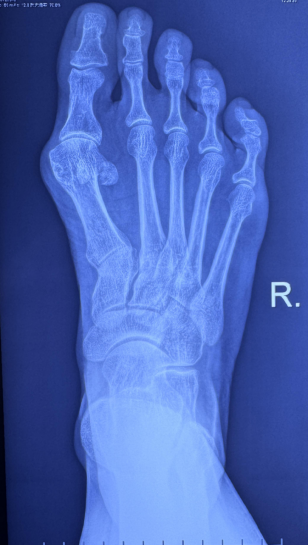

患者加拿大外籍女性,因 6 个月前出现右足大拇趾肿痛,活动受限,休息不见好转,保守治疗无效,于我院骨科门诊就诊,详细询问病史、查体、行右足 X-ray 检查提示右足拇外翻及第一跖趾关节轻度关节炎。故门诊以「右足拇外翻;右第一跖趾骨关节炎」诊断收住我院。

右足大拇趾外翻,第一跖趾关节红肿,压痛,第一跖趾关节轻度受限,趾端运动、感觉及血运良好。脊柱及其余四肢未见明显异常。

中度右足拇外翻:右第一跖趾骨关节炎。